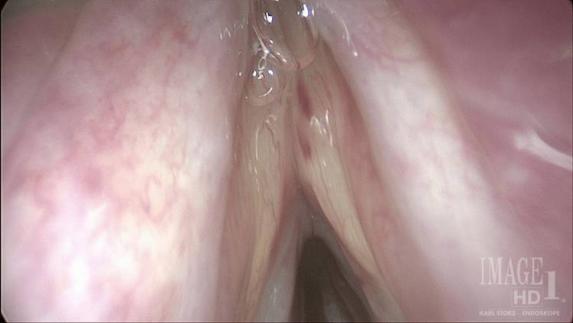

在几个月的时间里,患者接受了两次布地奈德鼻腔冲洗液、两次类固醇剂量包、阿奇霉素和莫米松冲洗液治疗鼻窦炎。在使用莫米松冲洗液时,布地奈德和抗组胺鼻喷雾剂停止使用。喉部检查发现双侧真、假声带水肿和声带振动无力伴肌肉紧张性发音障碍(图1)。

图1 喉镜检查发现双侧声带水肿